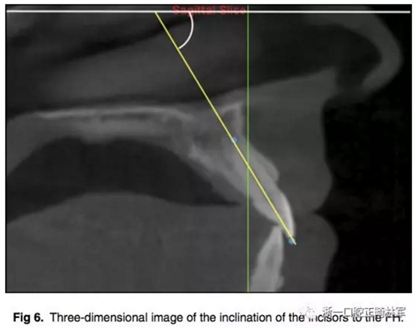

所有圖像導(dǎo)入Dolphin軟件中進(jìn)行處理,2D側(cè)位圖像為使用Dolphin軟件使用相同的標(biāo)準(zhǔn)切割CBCT獲得。使用眶耳平面(FH)作為水平參考平面,使用垂直于眶耳平面(FH)同時(shí)通過A點(diǎn)的直線作為垂直參考平面。在上切牙最前點(diǎn)進(jìn)行定點(diǎn),牙根分界為自釉牙骨質(zhì)界至根尖,在牙根根尖、牙長(zhǎng)1/2處、釉牙骨質(zhì)界下3mm處進(jìn)行定點(diǎn)。使用FH的平行線測(cè)量頰側(cè)牙槽骨至牙根上3點(diǎn)的距離,同時(shí)測(cè)量A點(diǎn)與以上三條線段的距離,如圖所示。測(cè)量切牙的轉(zhuǎn)矩,使用通過切點(diǎn)、根尖的直線與FH平面的所成角。

根據(jù)每顆切牙相對(duì)上頜骨的位置在同一平行切面上各自確定A點(diǎn),定好切牙最前點(diǎn)(MFMI),牙根長(zhǎng)度依然為釉牙骨質(zhì)界至根尖點(diǎn)。使用與2D側(cè)位片上相同的方法進(jìn)行牙根至骨皮質(zhì)的測(cè)量。轉(zhuǎn)矩的測(cè)量也同2D側(cè)位片。